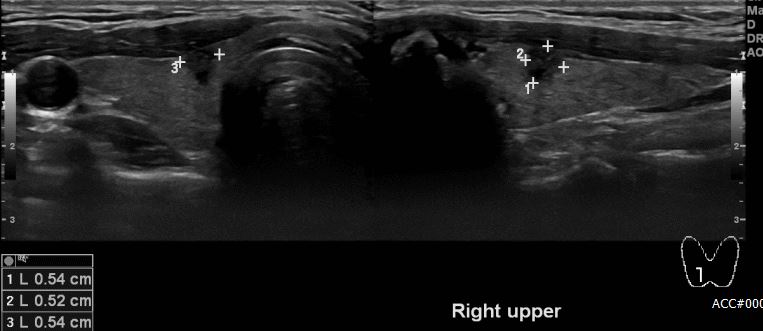

건강검진상 결절소견으로 내원하신 30대 남자환자분으로 본원에서 초음파시행후

우측갑상선의 의심스런 0.6cm 결절을 액상흡인세포병리검사 실시하여 갑상선유두암

진단되셨습니다.